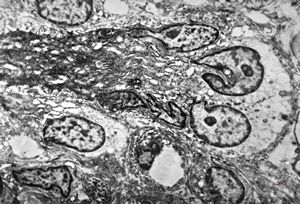

F,41y. | synovial metaplasia - capsule of implantate